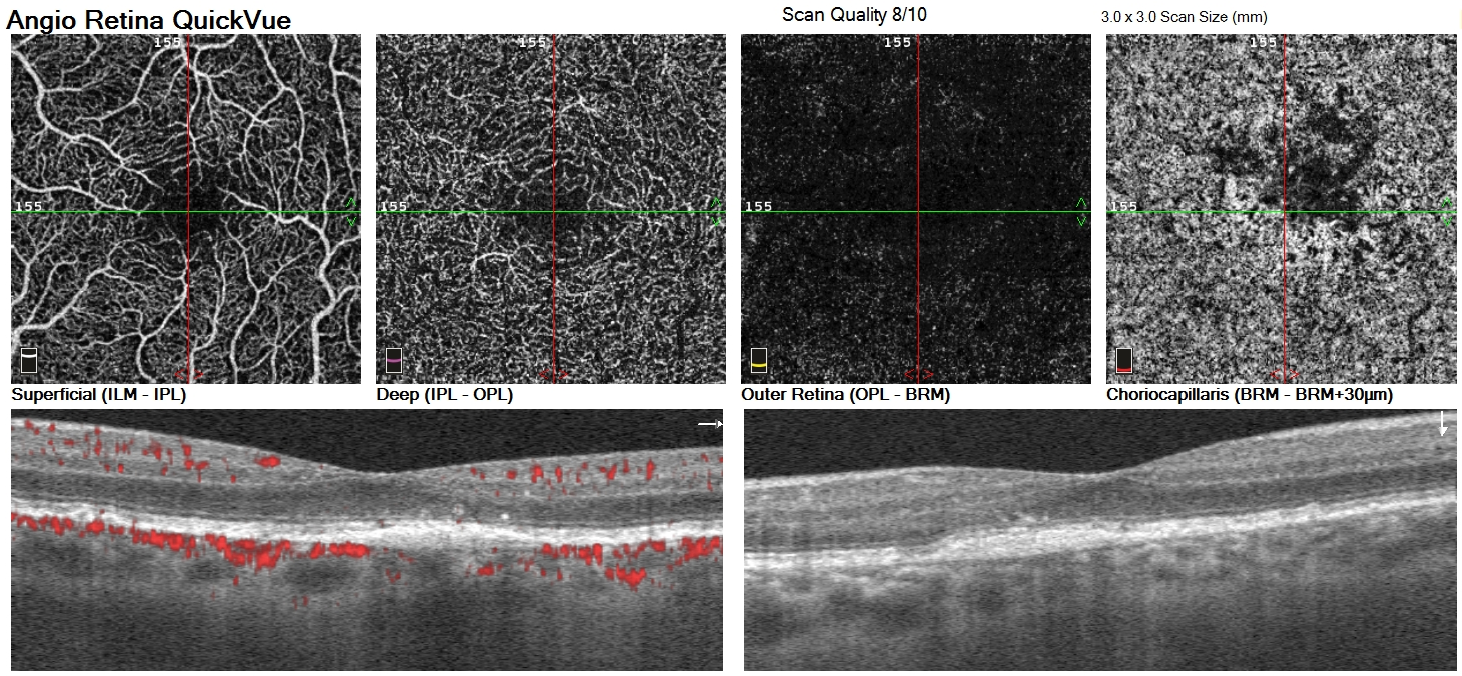

Streamline your ophthalmology practice and enhance patient consultations with our cutting-edge equipment. Experience a hassle-free workflow as our advanced technology empowers you to delegate data collection tasks to your skilled technicians.